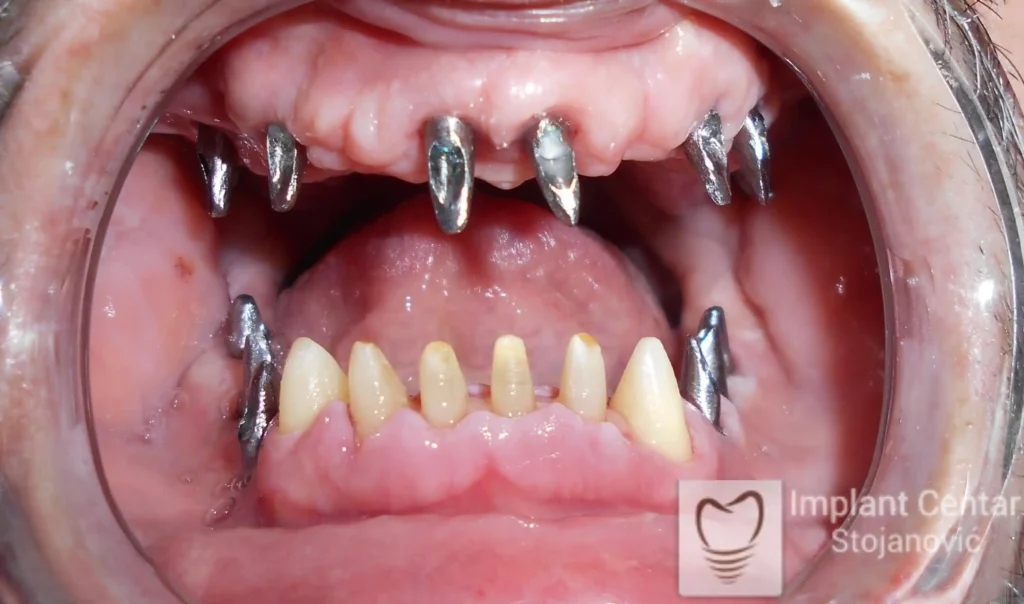

U ovom slučaju prikazujemo potpunu transformaciju osmeha pacijenta koji je imao obrnut zagriz koji smo rešili trajno i funkcionalno pomoću implantata.

Na slici 1. slici 2. vidi se početno stanje — pacijent je imao prirodne zube, ali samo izradom novih mostova nije bilo moguće postići normalan odnos gornjih i donjih zuba (eugnatan zagrižaj).

Zbog toga je plan terapije uključivao vađenje svih preostalih zuba i ugradnju implantata u gornjoj i donjoj vilici. U gornjoj vilici postavljena su i dva tuberopterigoidna implantata, kao zamena za sinus lift proceduru, što se može videti na ortopan snimku nurađenom odmah nakon ugradnje (slika 3).

Već tri dana nakon operacije, pacijent je zbrinut fiksnim privremenim zubima na implantatima, čime je odmah povraćena funkcija i estetika osmeha.

Nakon završetka perioda integracije implantata, izrađeni su cirkonijum-keramički mostovi u gornjoj i donjoj vilici (slika 6.).

Pacijent ističe da je prezadovoljan rezultatom — po prvi put nakon dugo vremena može normalno da žvaće i grize hranu, uz prirodan izgled novog osmeha.